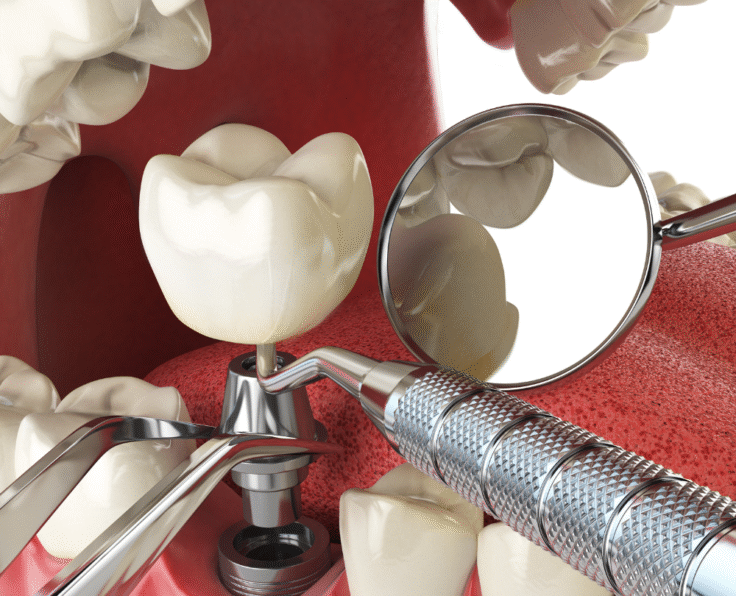

Dental Implants

Dental implants offer a strong, permanent replacement for missing teeth, ensuring a natural appearance and long-lasting oral stability.

Read More